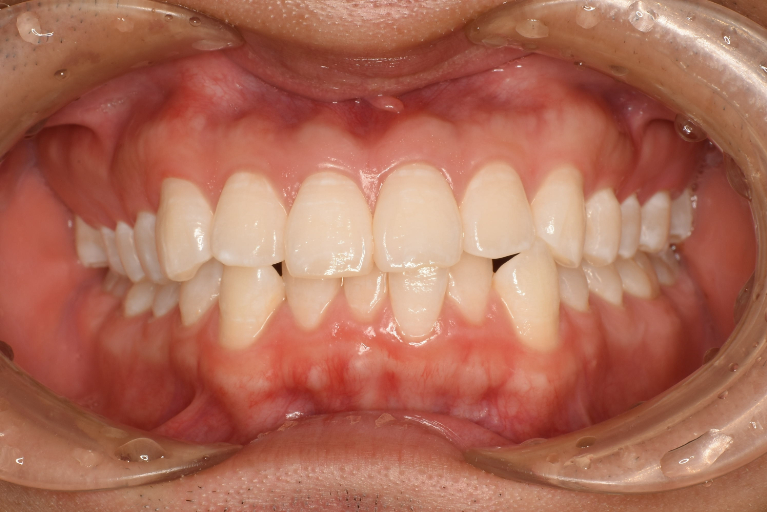

術前

術後

| 治療名 | インビザライン・ライト |

| 治療説明 | インビザラインを用いたマウスピース矯正により歯並びとかみ合わせの治療を行い、見た目と清掃性を改善しました。 |

| 治療回数・期間 | 4ヶ月 |

| 副作用とリスク | 矯正用マウスピースを20時間/1日装着して頂く必要があります。治療中は歯の移動による痛み、咬合時痛が生じることがあります。矯正治療により歯肉退縮、歯根吸収が起こるおそれがあります。マウスピースの数に限りがあるため適応できない場合があります。 |

| 料金(税込) | 治療計画作成料:55,000円 インビザライン矯正治療費:660,000円 リテーナー:55,000円 総額:770,000円 |